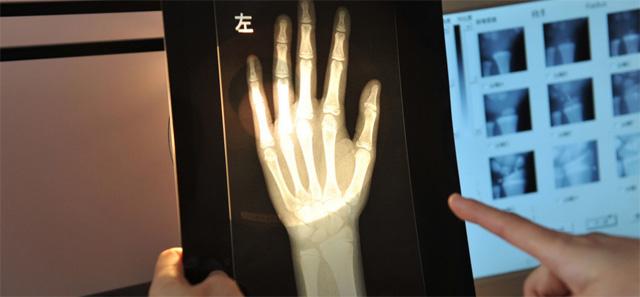

這個輻射到底對兒童有沒影響呢?其實影響不大的,預測孩子的骨齡是對身高的評估。怎樣監測,兒童在正常生長發育的過程中,隨著年齡的增加。骨骼線會逐漸的鈣化直至完全骨化,骨骼線閉合。骨齡是各個年齡骨的成熟度,正常情況下骨骼的年齡,和實際的年齡不應相差正負超過一歲。提前或者落後太多都是不正常的。用兒童的左手腕拍一張DR片來測骨齡,通過影像來觀測兒童骨骼生長發育情況。預測兒童的生長發育潛力。這個骨齡監測是比較準確的。

還有精準骨骼線檢查的位置在膝關節,通過DR拍片可以明確的看到骨骺線的狀態。這就是為什麽檢查了手掌的骨骼線還有檢查膝關節的。手掌的骨骼線閉合了,也不一定代表不能生長了,通過精準的骨骼線檢查,判斷兒童是否有長高的可能。膝關節骨骼線未閉合就可以進行身高的幹預治療。